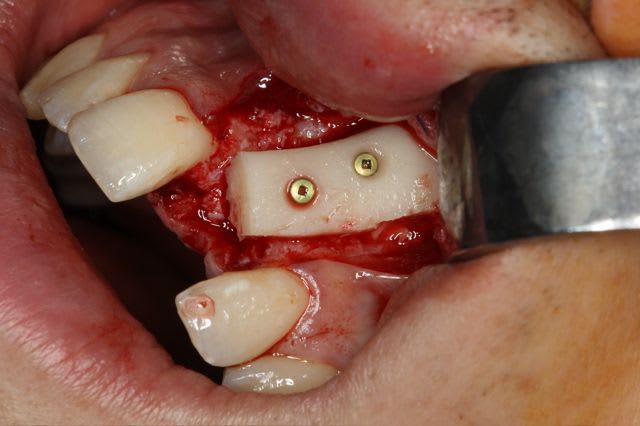

greffe onaly,

dépose des vis et pose de l'implant à 5mois1/2 avec un cj roulé et mise en place de la vis de cica,

pour la greffe: un lit de copeaux généreux et un bloc corticale par dessus et des copeaux pour boucher les espaces. Pas de membrane par dessus, seulement le périoste.